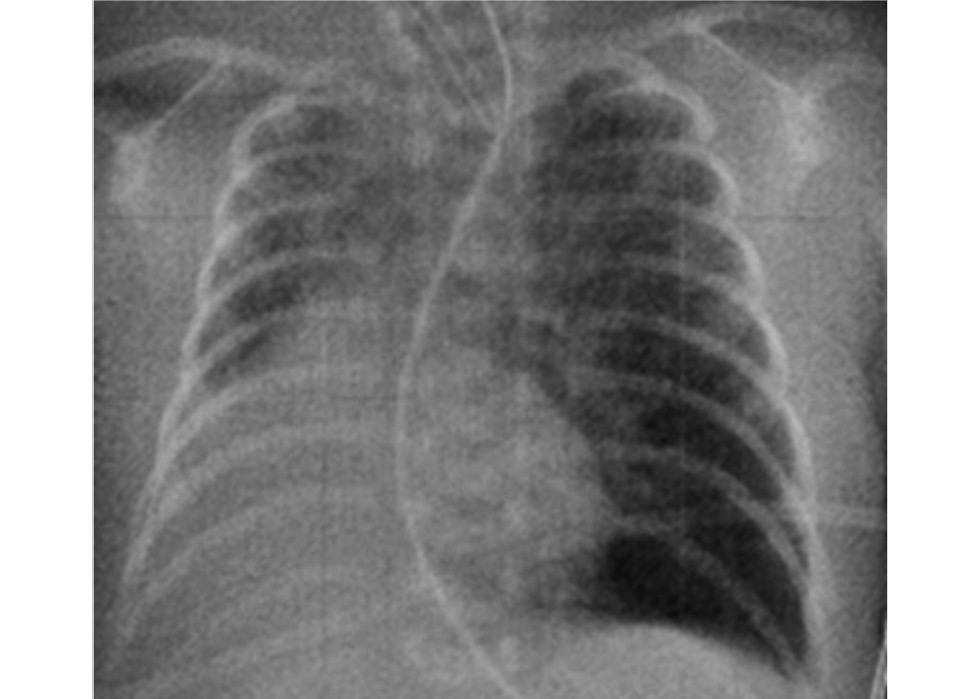

В течение последних 2 лет на фоне острых респираторных вирусных инфекций у девочки отмечались 3 эпизода бронхиальной обструкции. Кроме того, она перенесла лёгкую форму новой коронавирусной инфекции, лечение которой проводилось в стационаре. В дыхательной поддержке ребёнок не нуждался. Плановая рентгенограмма выполнена в возрасте 2,5 лет: оба лёгких пневматизированы (рис. 11).

Рис. 11. Рентгенограмма органов грудной полости в возрасте 2,5 лет.

Fig. 11. Chest X-ray at the age of 2.5 years.